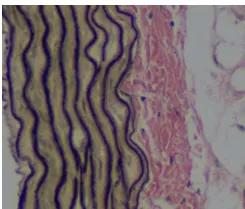

三、结果判读:

弹性纤维呈紫黑色,胶原纤维为红色,背景为黄色。

2、EVG染色:酒精苏木素:三氯化铁:碘液5:2:2混合成EVG染液,切片入EVG染

液染30 min,自来水冲洗。

3、背景分化:三氯化铁分化液稍分化一下,自来水洗一下,如此反复操作,在显微镜下

控制分化程度,至弹力纤维呈紫黑色,背景呈灰白色近无色。